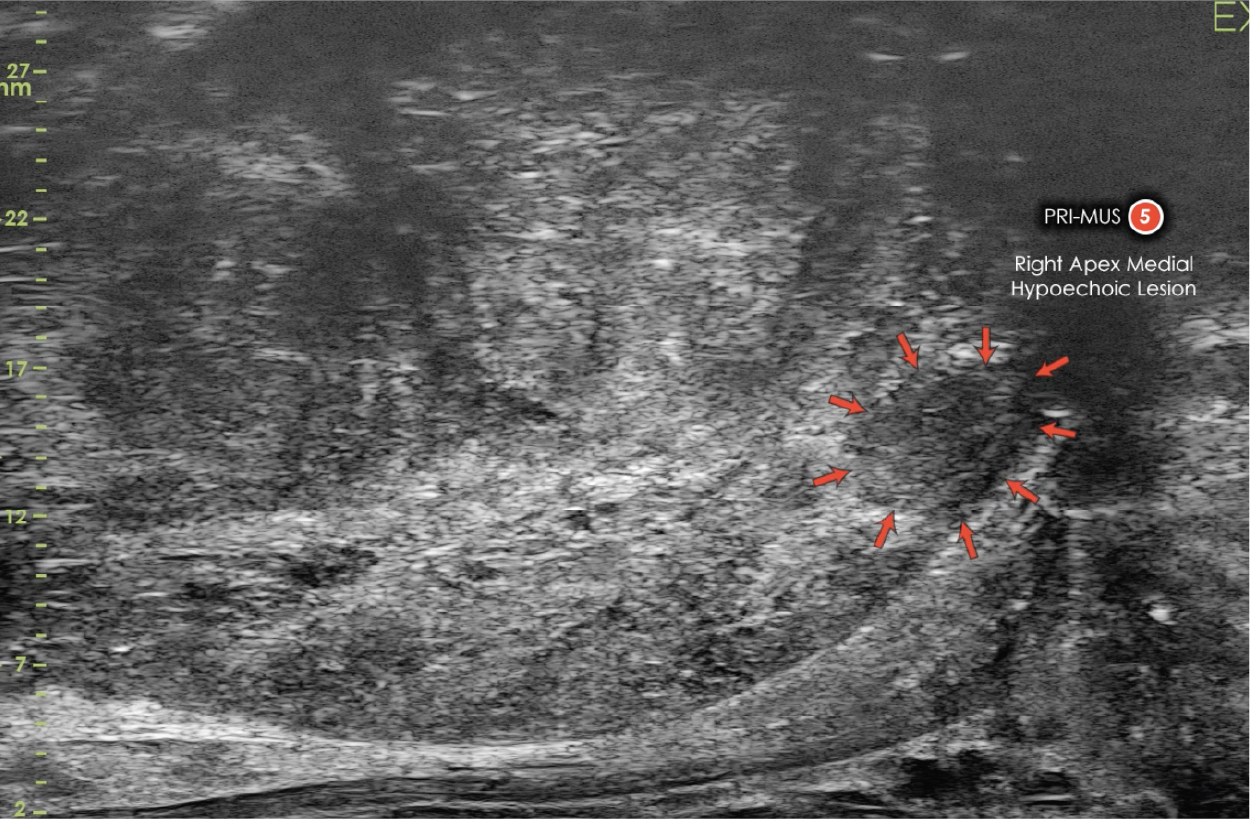

Differentiate Suspicious Regions assisted by the PRI-MUS evidence-based scale.

assisted by the PRI-MUS evidence-based scale.

Target in real-time

Urologists visualize suspicious regions and target biopsies with micro-ultrasound.